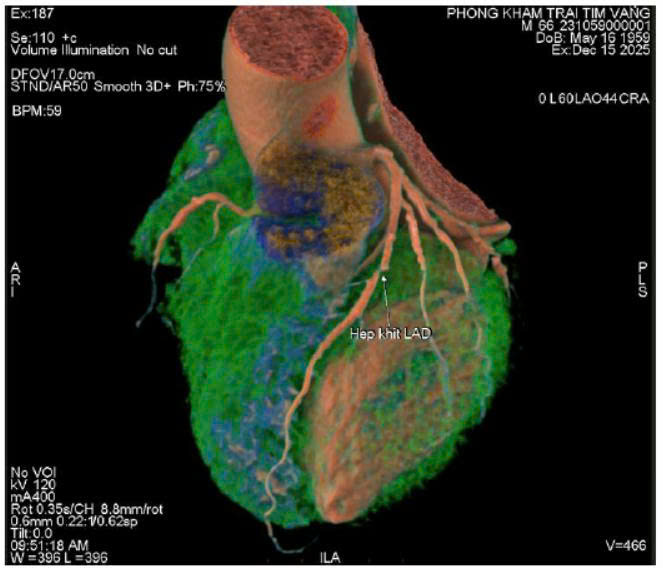

Nhiều bệnh nhân không có cơn đau tim rõ ràng, chỉ cảm thấy mệt, hụt hơi, tức ngực thoáng qua.

Tuy nhiên, khi kiểm tra chuyên sâu, bác sĩ phát hiện hẹp nặng động mạch vành LAD – nhánh mạch quan trọng nuôi tim.

- Khi mạch vành hẹp trên 70%, nguy cơ nhồi máu cơ tim tăng rõ rệt